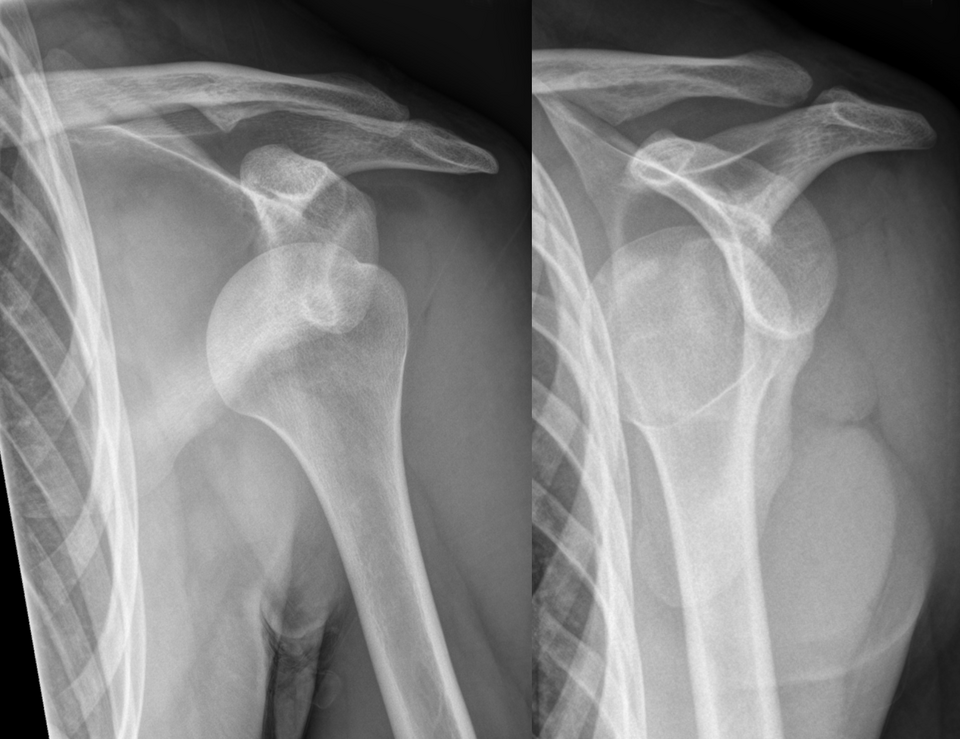

Dislocation Treatment

Rapid realignment after dislocation can prevent lifelong joint instability and pain

Why is physical therapy crucial after a joint dislocation is treated?

It immediately realigns the dislocated joint.

It helps restore strength and flexibility to prevent future dislocations.